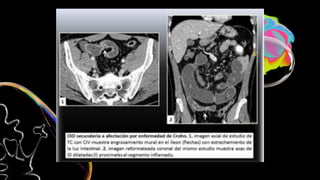

Asas dilatadas, colapsadas

o de calibre normal

Engrosamiento con

hipocaptacion de la pared

Ingurgitacion de vasos

mesentéricos

Obstrucción en asa cerrada

Colapso intestinal

Gas en sistema portal o

neumoperitoneo